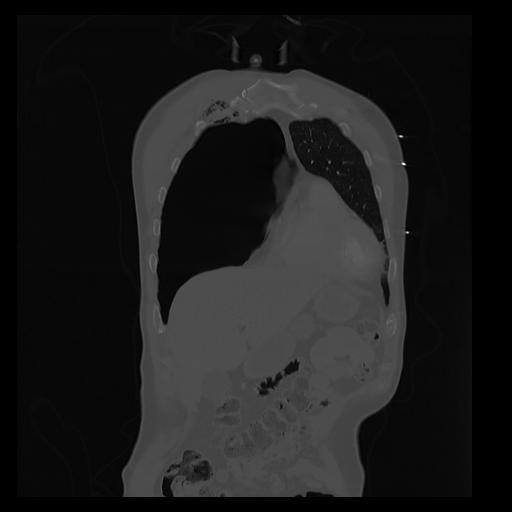

32 PULMON,CE,Coronal,3.000,PULMON,Coronal,